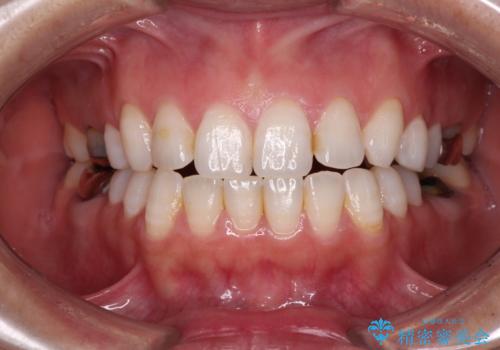

- 奥歯の銀歯が外れたことをきっかけに、全ての銀歯をセラミックに替えたいとのことで来院された患者様です。

第一大臼歯4本と、メタルインレーが装着されている2歯をセラミッククラウンならびにセラミックインレーにて補綴治療・修復治療を行うこととしました。

口腔内から、土台も含め銀歯がなくなったことでメタルフリーとなりました。